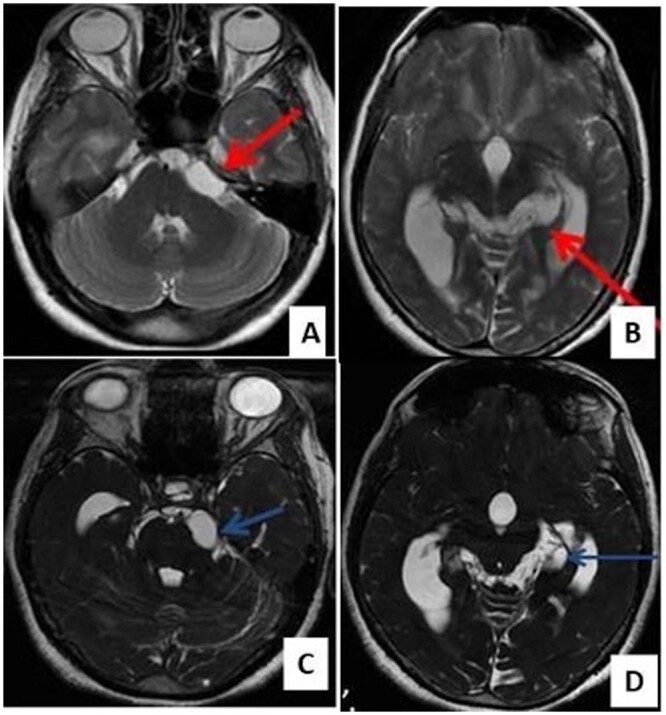

神经囊尾蚴病(NCC)是世界某些地区常见的中枢神经系统寄生虫病。总状型神经囊虫病与常见的实质型神经囊虫病截然不同。它经常浸润基底蝶窦和西尔维窝。影像学检查在诊断中起着至关重要的作用;然而,由于其信号强度与脑脊液相似,而且在大多数病例中没有增强,因此常规 MRI 序列的影像学诊断往往比较困难。在此,我们介绍了五例消旋体 NCC 病例,以强调重 T2 加权序列(快速成像稳态采集)序列在诊断这种疾病中的重要性。

Neurocysticercosis (NCC) is a common parasitic condition of the central nervous system in certain parts of the world. The racemose variety of NCC is distinct from the commonly seen parenchymal form. It frequently infiltrates the basal cisterns and Sylvian fissures. Imaging plays a vital role in the diagnosis; however, as their signal intensity is similar to cerebrospinal fluid and due to the absence of enhancement in most cases, imaging diagnosis is often difficult on the conventional MRI sequences. Here, we present five cases of racemose NCC to emphasize the importance of a heavily T2-weighted sequence (Fast Imaging Employing Steady-state Acquisition) sequence in the diagnosing this entity.